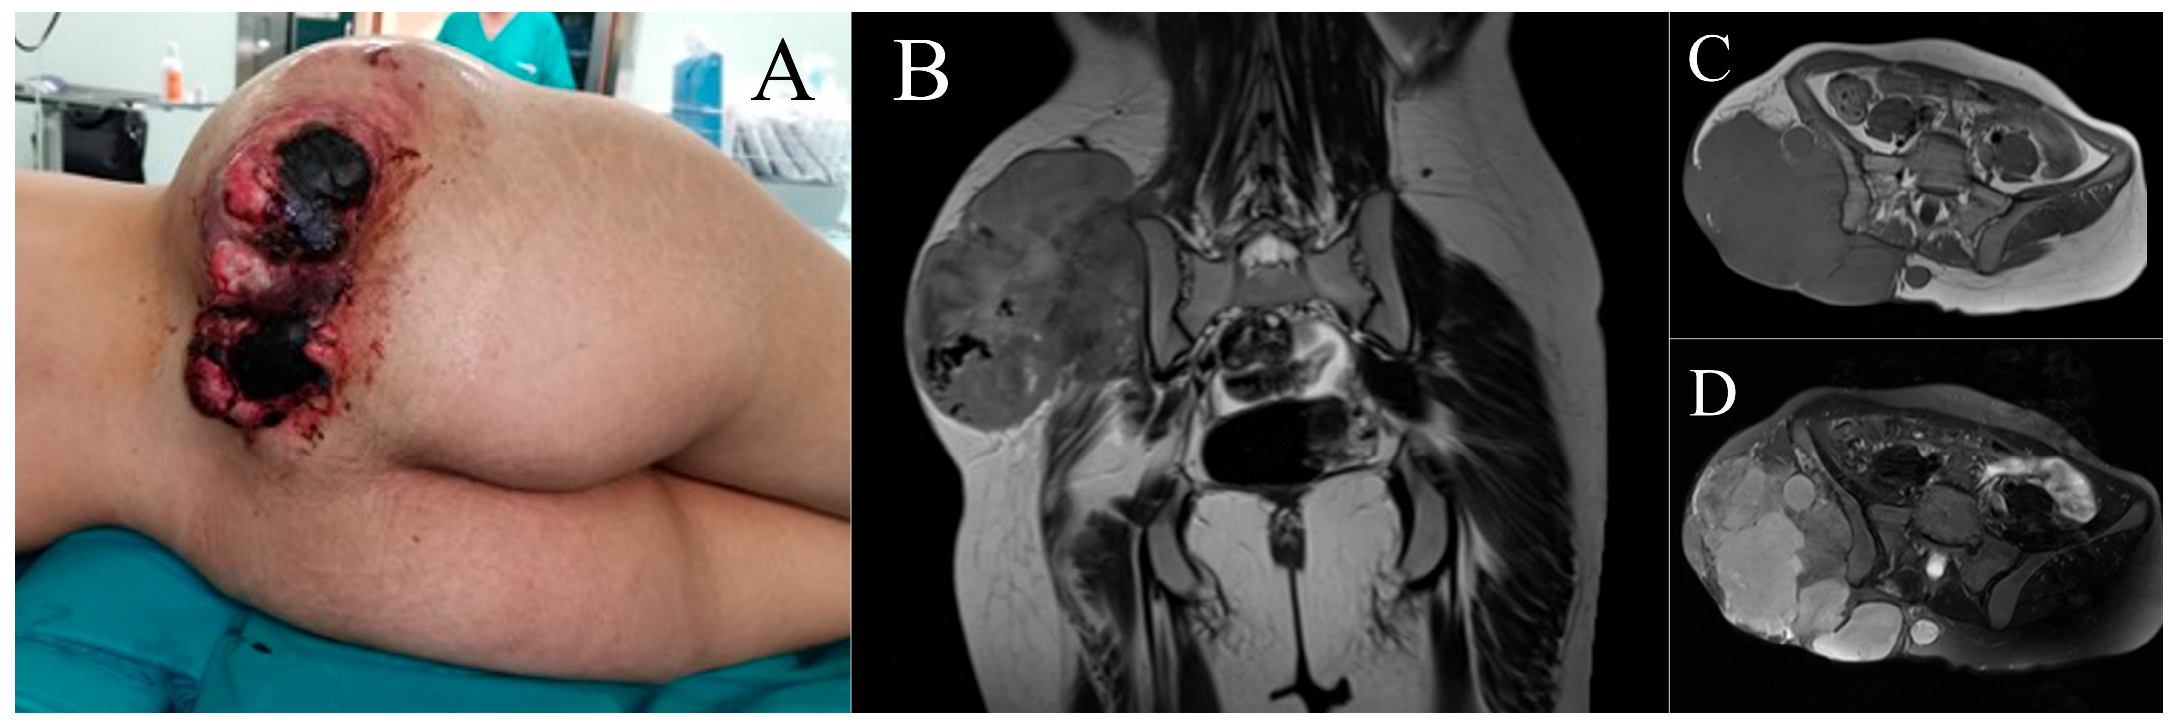

2.1. Case 1

2.2. Case 2

3.1. Case 1

3.2. Case 2